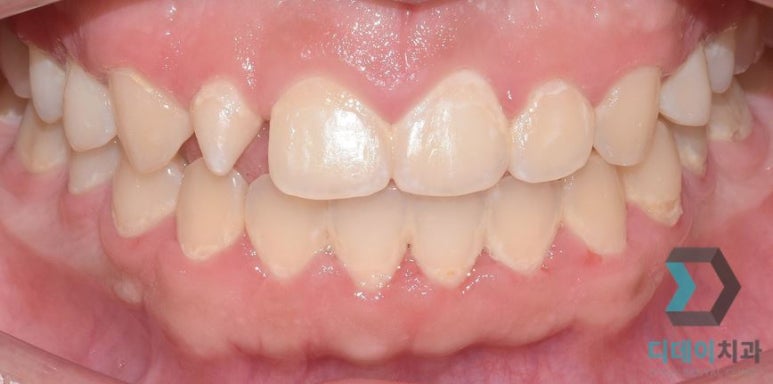

(전) 2021-11-20, (후) 2021-11-30

과도하게 자란 잇몸으로

치과용 레이저로 잇몸성형 진행

(전) 2022-02-14, (후) 2022-02-28

치아를 덮고 있는 잇몸라인을 높여주어

대칭을 맞춰준 모습

사진에서처럼 잇몸라인을 정리해 준 것만으로도 치아가 시원하고 커 보이는 것을 확인하실 수 있을 것입니다.